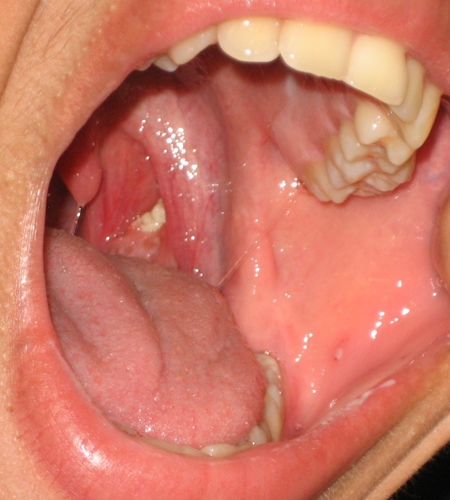

Picture of left tonsil showing tonsil stone

Picture of left tonsil showing tonsil stone (taken from File:Tonsillolith in mouth.jpg - Wikimedia Commons) http://creativecommons.org/licenses/by-nc-sa/3.0/